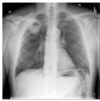

pointing at what, what is this called

thymus: sail sign

what is the finding

what disease is this finding associated with

thymoma (an anterior mediastinal mass)